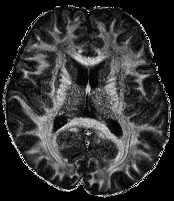

The super resolution image in 6(a), serving as a reference here, was obtained using the super-resolution reconstruction technique that combines multiple thick-slice DWI with all 60 diffusion directions into a high-resolution image, cf. (citep \@BBN(Ramos-Llordén et al., 2020)). This technique yields a high quality image with good detail preservation, but takes much longer scan time than the standard upsampling method in 6(c), where the FA map of the low-resolution data was up-sampled using 3DSlicer (citep \@BBN(Fedorov et al., 2012)) to the higher resolution.

The image in 6(b), cf. (citep \@BBN(Ning et al., 2016)), was obtained using a combined super-resolution reconstruction, compressive sensing, and spatial regularization techniques with thick-slice images, where each thick-slice DWI has a different set of 20202020 diffusion gradient directions, saving indispensable scan time. The advanced method yields a much higher visual quality image than 6(c), preserving more anatomical details.

Refer to caption

(a) Reference

(b) (17.62, 0.57, 0.19)

(c) (18.23, 0.58, 0.26)

Figure 6: Visualized FA images obtained from diffusion MRI with super-resolution reconstructions. The up-sampled image (c) with lower resolution is wrongly judged to have better quality than the high-resolution reconstruction (b) by PSNR and SSIM, LPIPS judges this task correctly.

FR-IQA mismatch

We can see in Figure 6 that PSNR and SSIM misjudge the visual quality of the high-resolution reconstruction in (b) in comparison to the up-sampled image in (c). The image is per default more blurry and does not provide sufficient anatomical details and therefore offers worse visual quality than the reconstruction in (b). LPIPS yields more sufficient results in this example, and correctly attributes (c) a higher quality error.

In this example, it has to be noted that the computed IQA numbers are generally quite low, because the resulting FA images do not necessarily have the same range or distribution as the reference image. Therefore, in order to compare the reconstruction quality directly, this task generally benefits from NR-IQA evaluation.